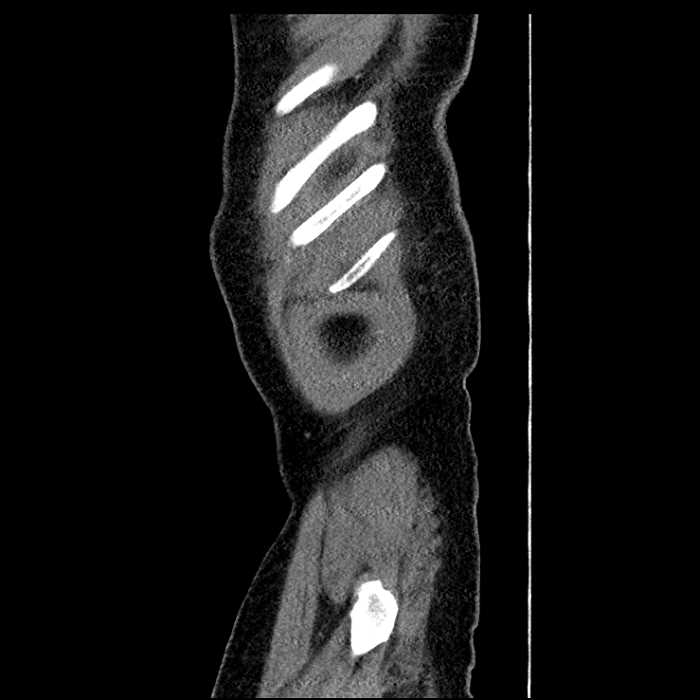

• Large fluid density structure in hepatic segments 7 and 8 measuring 10 x 7 x 7 cm with internal septation and circumferential ill-defined low density compatible with edema

• Peripherally enhancing subcapsular collections along the anterior margin of the left hepatic lobe measuring 3 x 1 cm and 2 x 1 cm

Acute sigmoid diverticulitis complicated by a small contained perforation and a large abscess in the right hepatic lobe. Additional small subcapsular abscesses along the anterior margin of the left hepatic lobe.

• The classic CT imaging appearance is a double target sign with internal low density surrounded by an internal enhancing rim (capsule) and a low density external rim (edema)

Hepatic abscess showing the double target sign with low density internally surrounded by a thin inner enhancing rim (red arrow) and ill-defined outer low density rim (yellow arrow). Blue arrow indicates an internal septation. Red arrows: additional smaller subcapsular abscesses. Red arrow: focal contained perforation associated with diverticulitis.